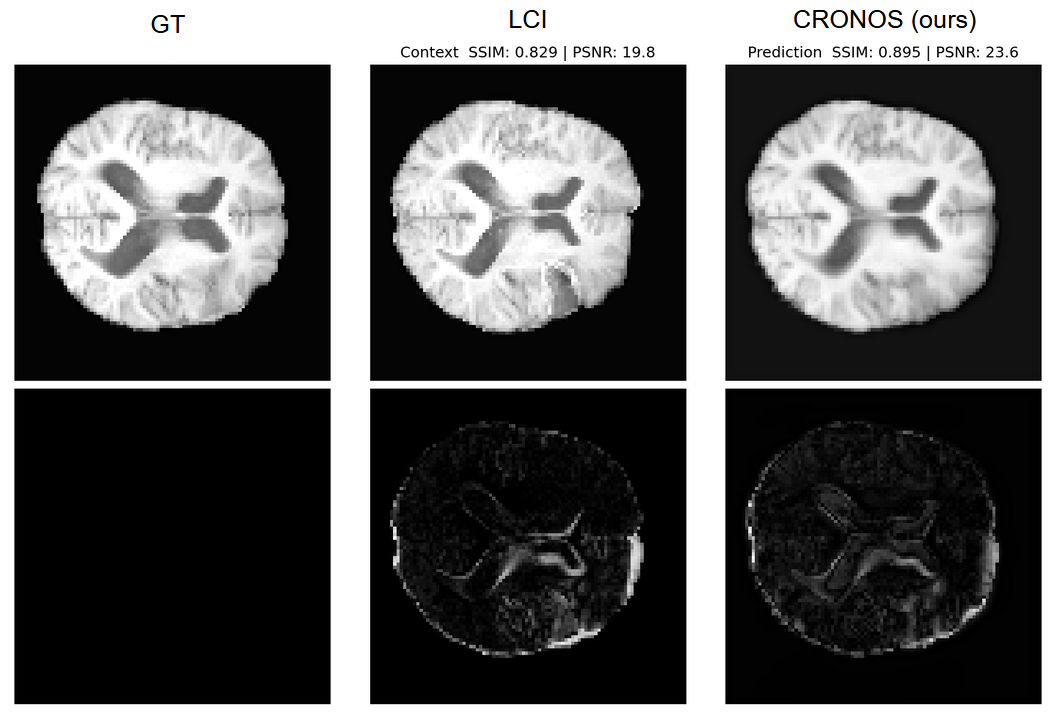

Figure 3: Qualitative comparison on the ACDC dataset. Ground truth (GT), Last Context Image (LCI), our method (CRONOS), and SimVP. Upper row: prediction, lower row: residuals.

Figures 36 and  4 highlight qualitative comparisons, as well as dataset examples. The LCI baseline often appears visually close to the target, largely because many longitudinal scans exhibit only subtle changes. However, e.g. SimVP tends to introduce artifacts and blur anatomical details. In contrast, CRONOS yields sharper reconstructions and consistently lower residuals compared to LCI, highlighting its ability to capture fine-grained temporal progression.